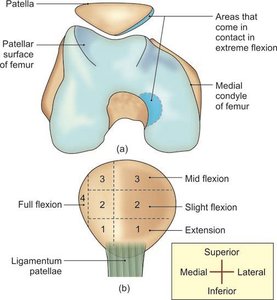

The knee joint is the largest and most complex joint in the human body, essential for weight-bearing and movement. It is classified as a condylar synovial joint, incorporating two condylar joints between the femur and tibia, and a saddle joint between the femur and patella. The joint cavity is divided by the menisci, making it a complex joint.

Articular surfaces: Formed by the condyles of the femur, the patella, and the condyles of the tibia.

Movements at the Knee Joint

The knee joint allows several movements, primarily flexion and extension, as well as limited medial and lateral rotation. These movements are essential for walking, running, and standing.

Flexion: Bending the knee, decreasing the angle between femur and tibia.

Extension: Straightening the knee, increasing the angle.

Medial rotation: Rotating the tibia inward (occurs in flexed position).

Lateral rotation: Rotating the tibia outward (occurs in flexed position).

Flexion and extension occur in the upper compartment; rotation occurs in the lower (meniscotibial) compartment.